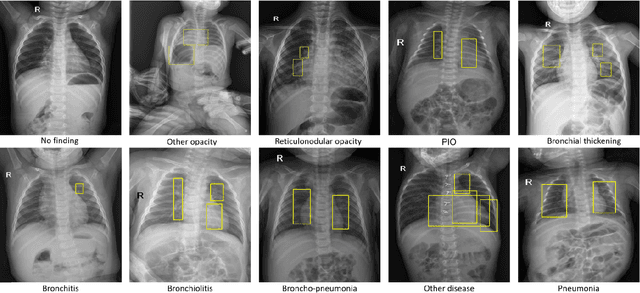

Abstract:Computer-aided diagnosis systems in adult chest radiography (CXR) have recently achieved great success thanks to the availability of large-scale, annotated datasets and the advent of high-performance supervised learning algorithms. However, the development of diagnostic models for detecting and diagnosing pediatric diseases in CXR scans is undertaken due to the lack of high-quality physician-annotated datasets. To overcome this challenge, we introduce and release VinDr-PCXR, a new pediatric CXR dataset of 9,125 studies retrospectively collected from a major pediatric hospital in Vietnam between 2020 and 2021. Each scan was manually annotated by a pediatric radiologist who has more than ten years of experience. The dataset was labeled for the presence of 36 critical findings and 15 diseases. In particular, each abnormal finding was identified via a rectangle bounding box on the image. To the best of our knowledge, this is the first and largest pediatric CXR dataset containing lesion-level annotations and image-level labels for the detection of multiple findings and diseases. For algorithm development, the dataset was divided into a training set of 7,728 and a test set of 1,397. To encourage new advances in pediatric CXR interpretation using data-driven approaches, we provide a detailed description of the VinDr-PCXR data sample and make the dataset publicly available on https://physionet.org/.